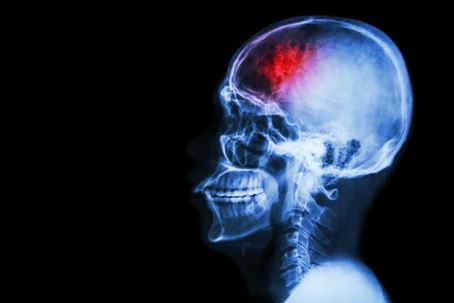

What is a Brain Injury?

Brain injuries can occur at any point in one’s life, and can even occur prior to birth. Brain injuries are considered either Traumatic Brain Injuries or Non-Traumatic Brain Injuries, depending on the cause. Traumatic Brain Injuries (TBI) are caused by external trauma to the head, such as a fall or other type of impact. Non-Traumatic Brain Injuries (non-TBI) are caused by internal factors that change the functioning of the brain, such as a lack of oxygen. A brain injury of any type can have severe, debilitating effects, and is often permanent.